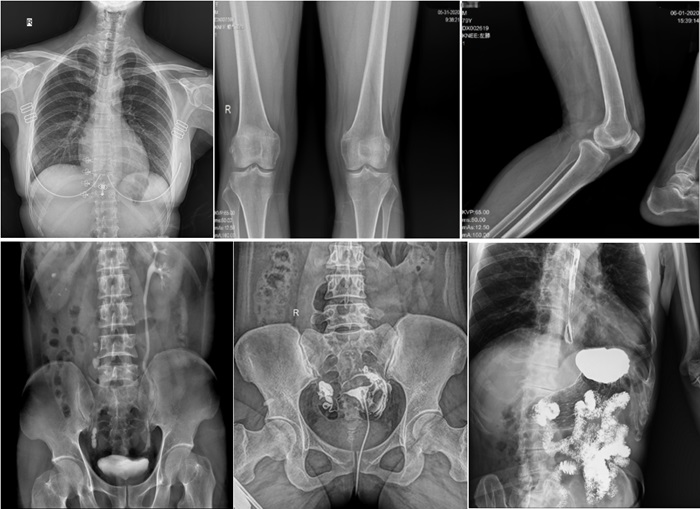

普利德動態(tài)平板DRF作為普放領(lǐng)域最新技術(shù)的代表,融合了攝影、透視和造影等多功能于一體,并能在可視化條件下進(jìn)行高清點片,有效減少了傳統(tǒng)靜態(tài)DR盲拍造成漏診和誤診的風(fēng)險。其17×17英寸大幅面成像,能夠通過一次曝光實現(xiàn)胸部、腹部覆蓋。設(shè)備支持最高30/秒的采集幀率,確保了動態(tài)影像的流暢性,便于醫(yī)生觀察細(xì)微病變,提升診斷精準(zhǔn)性。

在實際應(yīng)用中,普利德動態(tài)平板DRF展現(xiàn)出了多種優(yōu)勢。例如,在胸部影像檢查中,它清晰顯示肺部紋理和結(jié)節(jié),為肺癌早期篩查提供有力支持;在骨科領(lǐng)域,可用于骨折的診斷和復(fù)位效果評估,幫助醫(yī)生制定更精準(zhǔn)的治療方案;在消化系統(tǒng)檢查中,能有效發(fā)現(xiàn)胃腸道疾病的異常。

在婦科方面,不僅能夠直觀的觀察子宮形態(tài)、大小,輸卵管各部有無扭曲、管腔粘連以及梗塞情況,還可以在加壓推注下,使部分輸卵管輕、中度堵塞的患者得以通暢,起到有效的治療作用。